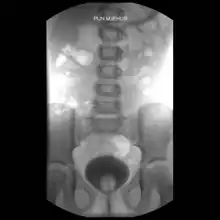

The cause is unclear.[1] The more severe forms of disease occur more commonly when there is a lack of folate before pregnancy.[1] Diagnosis is based on examination.[1] An X-ray is recommended to find associated pubic diastasis.[1]

Diagnosis is based on examination.[1] An X-ray is recommended to find associated pubic diastasis.[1]